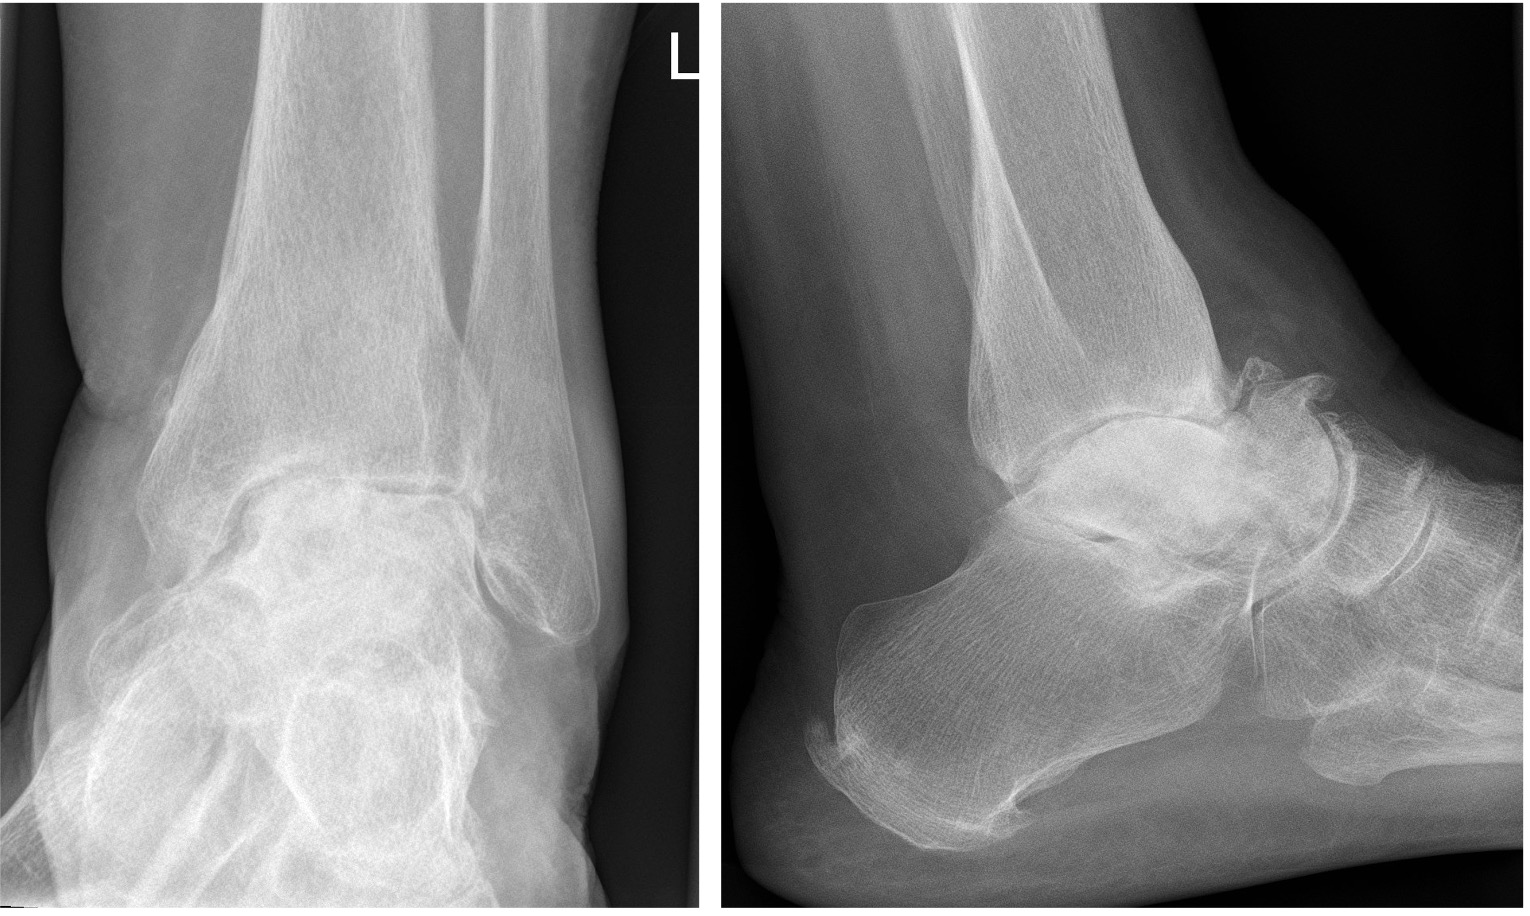

- CT to assess arthrosis & function between normal/abnormal architecture (Figure 15)

Figure 15: CT slices showing avascular necrosis of the talus and tibial plafond resulting in a severe valgus deformity